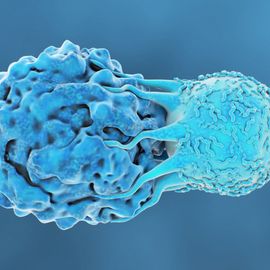

Cancer Immunology

This page provides educational resources, events, news and products related to cancer immunology. Content will cover aspects from the tumor immune environment and immunosurveillance, to cancer immunotherapies and vaccines.